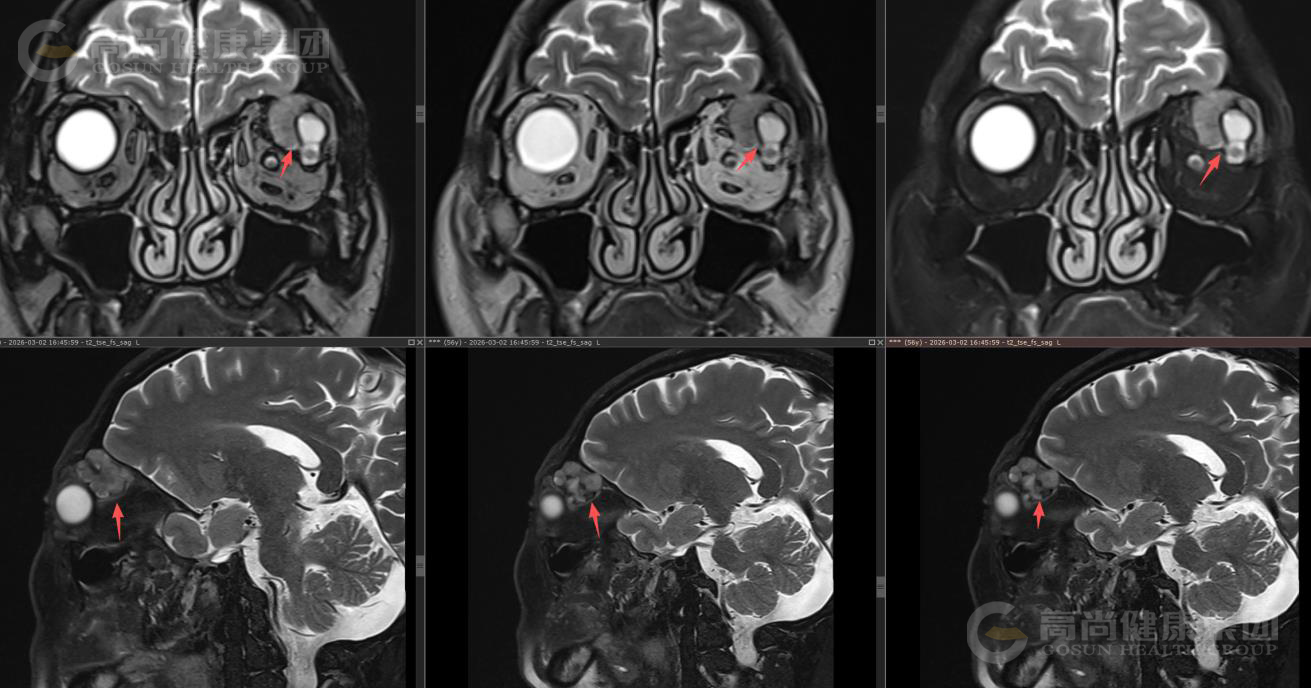

眼眶MR平扫+增强扫描

序列 T1WI T2WI T2WI-FS DWI/ADC T1-VIBE+C 3D-T1WI+C

方位 TRA SAG COR

左眼眶外上泪腺区类圆形异常信号影,大小约23×26×26mm(左右径×前后径×上下径),呈囊实性改,T1WI呈等信号,T2WI及T2WI-FS序列主要呈稍高信号伴囊样高信号,实性部分DWI呈轻度高信号,囊性部分呈等信号,ADC实质部分呈低信号,囊性部分呈高信号。

MR增强扫描: 肿块实质部分呈明显强化,且持续强化,囊变区不强化,病灶累及左眼眶肌锥内外间隙,与邻近泪腺界限不清,左侧眼球受压、向前突出,左侧上直肌、外直肌轻度受压。

影像诊断结果: 左侧泪腺区肿瘤性病变,考虑泪腺混合瘤,部分囊变坏死,不除外其它,请结合临床。